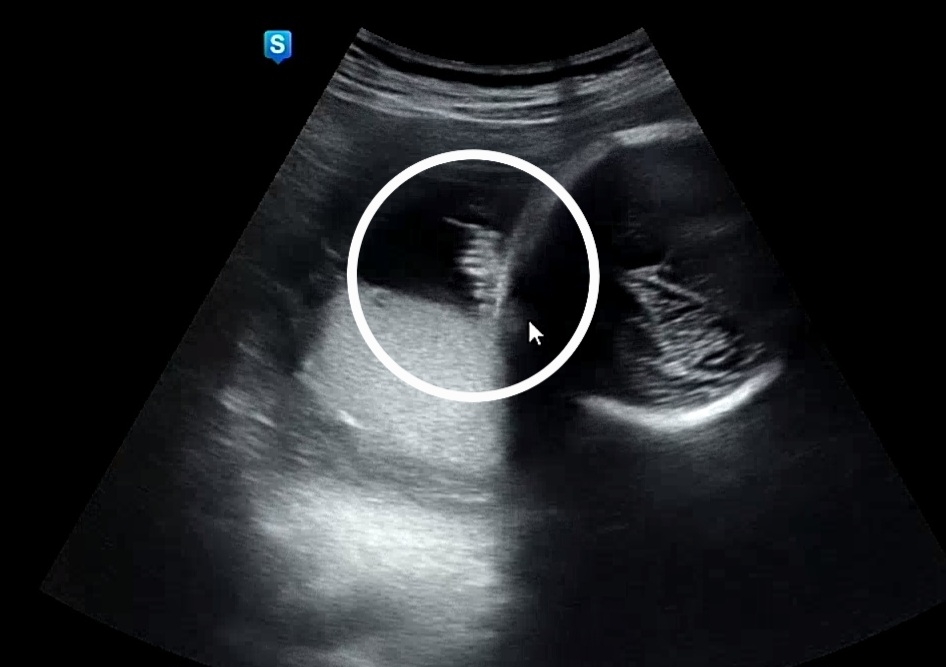

30주4일 병원가서 백일해 주사 맞고 왔어요~(5만) 남편은 35주쯤 맞으라고 하네요 오늘 초음파 보는데 애기 머리카락이라고 알려주셨어요ㅋㅋ 양수 속에서 흩날리는 머리카락 신기해서 올려봐요 ><ㅋㅋ

초음파 머리카락 ㅋㅋ